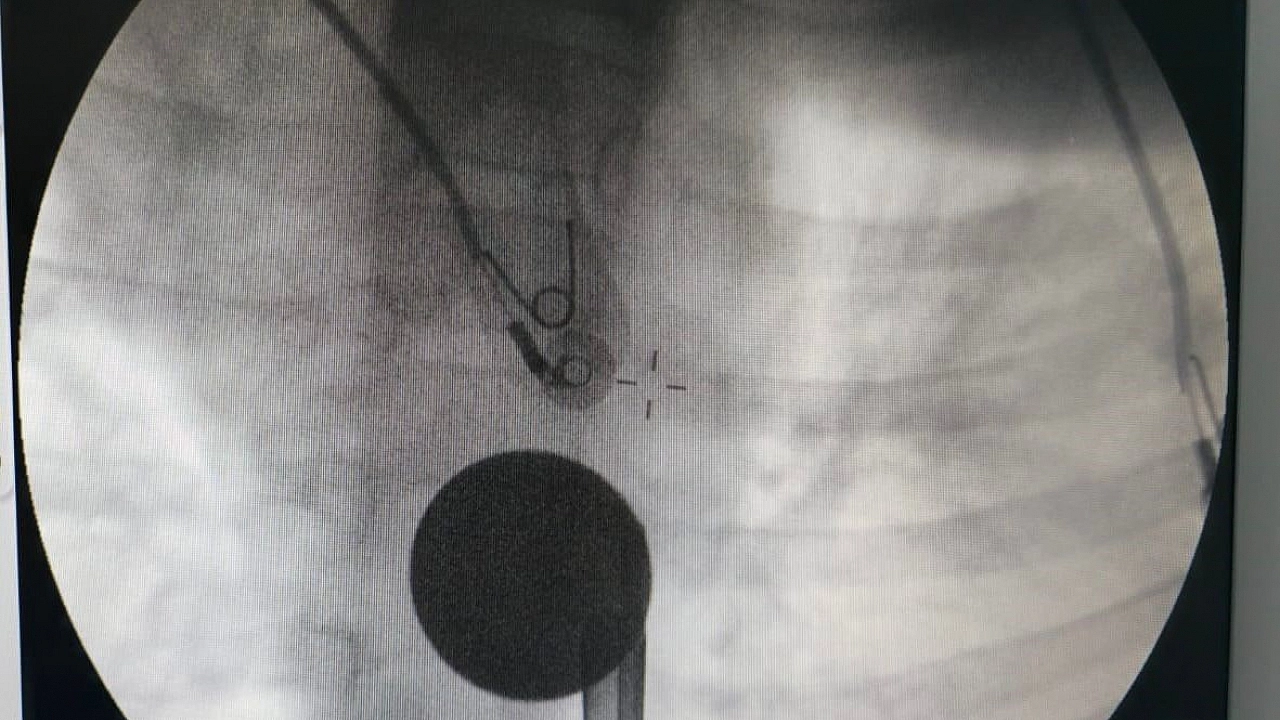

Yabancı cisim yutma şikayetiyle ailesi tarafından Siirt Eğitim ve Araştırma Hastanesine getirilen 8 yaşındaki Y.K., yapılan ilk değerlendirme ve görüntüleme tetkiklerinin ardından ilgili branşlarca operasyona alındı. Y.K.’nın yemek borusuna kadar ilerlediği tespit edilen madeni para, gastroenteroloji uzmanı Dr. Yaren Dirik ve kulak burun boğaz hekimi Yasin Gökçınar tarafından müdahale edilerek çıkartıldı. Operasyonun ardından bir süre gözlem altında tutulan Y.K., tedavisinin tamamlanmasıyla taburcu edildi.

Siirt Eğitim ve Araştırma Hastanesi Başhekim Yardımcısı Uzman Dr. Burak Özkan, çocuk hastalarda yabancı cisim yutma vakalarının ciddi riskler oluşturabileceğini söyledi. Uzm. Dr. Özkan, "Hastanemize başvuran 8 yaşındaki hastamızın yemek borusuna kaçan madeni para, gastroenteroloji ve KBB ekiplerimizin koordineli ve titiz çalışmasıyla herhangi bir komplikasyona yol açmadan başarılı bir şekilde çıkarılmıştır. Operasyon süreci sorunsuz geçmiş olup hastamızın genel durumu iyidir" dedi.